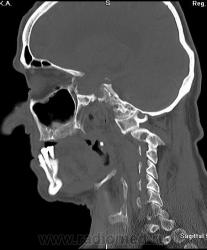

Мужчина, весьма преклонного возраста, обратился на прием в поликлинику в сопровождении родственников. Предъявляет жалобы на головную боль, плохую память, Направлен неврологом на КТ головного мозга.

Но были обнаружены изменения, и в шее, которые, явились случайной находкой. Анамнез собрать было проблемно, с памятью у пациента - "совсем плохо". Родственники отмечают (мужчина живет один в деревне), что несколько месяцев тому мужчина упал и разбил голову, было много крови.

Перелом основания зуба С2 со смещением вперед....

Главная опасность - это сужение позвоночного канала между фрагментами позвонков. Поперечное сечение спинного мозга на уровне шеи около 13 мм, если расстояние меньше, как в этом случае, - возможна быстрая гибель спинного мозга...

Сначала было исследование головного мозга, от С1 до макушки. Мне не понравилась "теснота" в задней черепной ямке, т. е. суженные субарахноидальные щели, и это на фоне атрофиченских изменений. Взглянув на боковую топограмму, решила сделать и шею. На тот момент указаний на травму не было. Только попытав дочь пациента удалось установить факт травмы. Парезов и параличей нет. Нейрохирурги отправили пациента домой, посоветовали носить воротник.